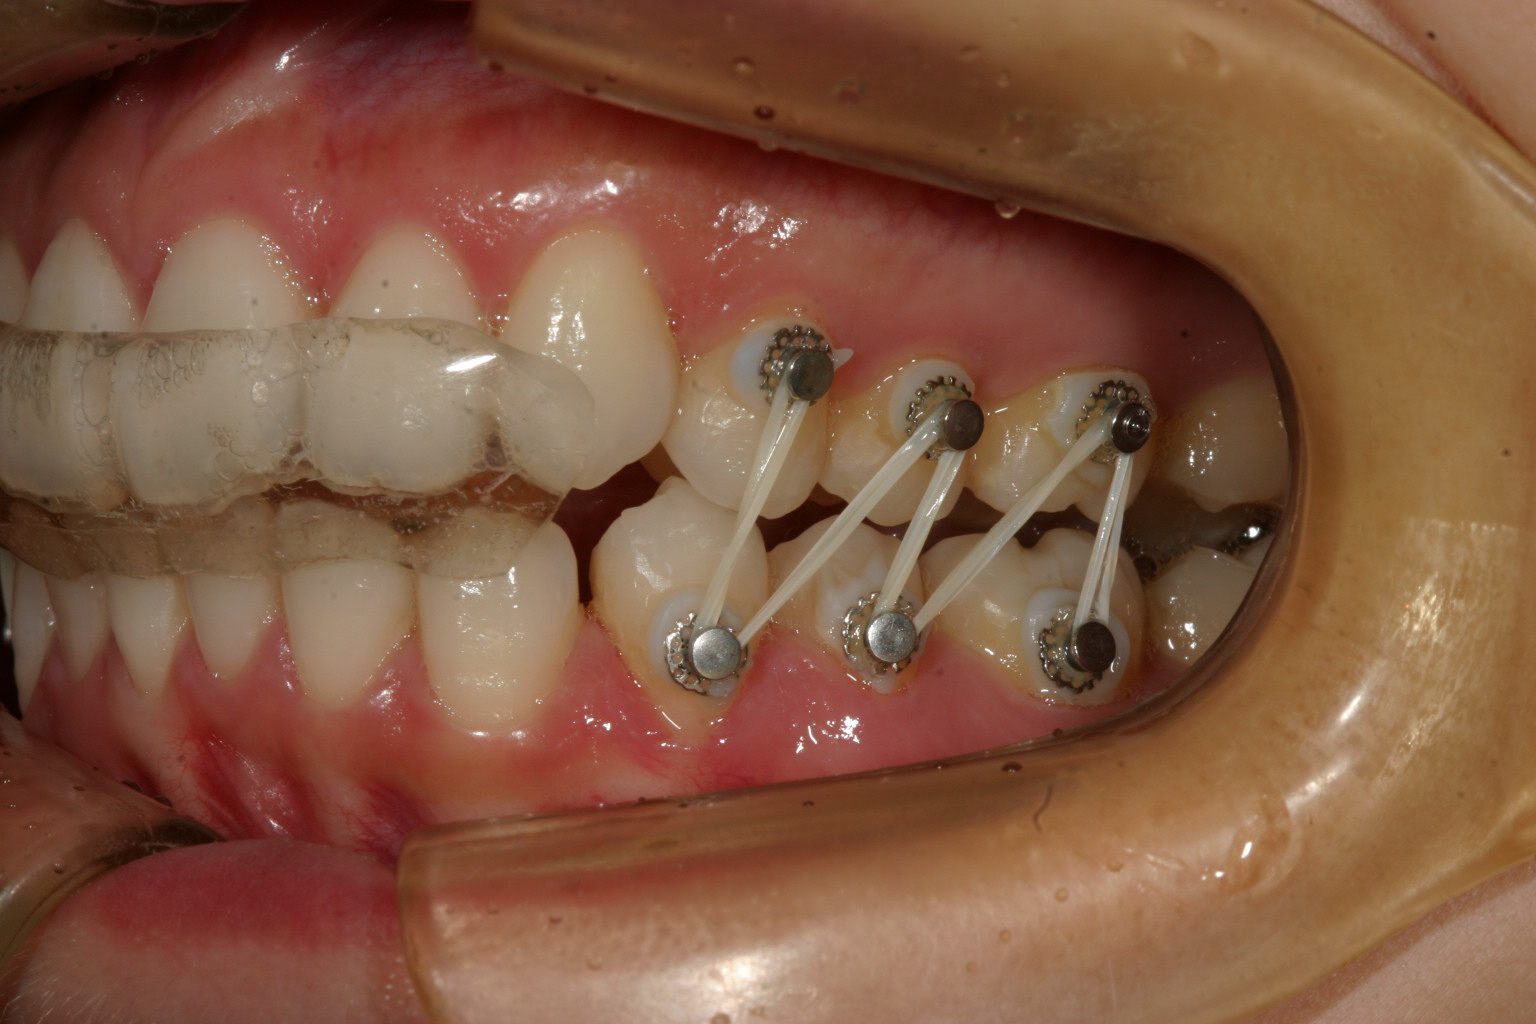

アップダウンエラスティックの右側です。

アップダウンエラスティックの左側です。